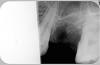

Doc Опубликовано 9 мая, 2009 Поделиться Опубликовано 9 мая, 2009 Вот точные копии всего, что было: На сайте клиники было размещено вот это: Клиника Коллонтай 17, сумма 2800. Было удаление зуба, врач хирург удалил зуб и наложил швы. Хирург не назначил повторную дату осмотра. в результате образовалась опухоль и начались гнойные процессы,при обследовании в другой клинике,на основании снимка и диагностики врача пришлось делать полную чистку лунки.При чистке была извлечена киста,остатки корня,стенки зуба и большое количество оставленных осколков. Если бы вовремя не обратились в другую клинику то нагноения пошли бы в гайморову пазуху. За работу пришлось еще отдать 1800. Такого раздолбайства еще не встречала. Обратного адреса не было, имя было подставное. То есть, анонимка. В базе я не нашел такой суммы, позже выяснилось, что еще и сумма была написана неправильно, на деле там было 2512 рублей. Обычно анонимки не рассматриваются, но в данном случае я решил дать человеку шанс. Это сообщение не было стерто, как утверждают некоторые. Наоборот, на него был дан ответ и оно было опубликовано на сайте в разделе Вопросы-Ответы с просьбой сообщить подробности, обещанием разобраться в вопросе и вернуть деньги в случае, если будет доказана хоть малейшая вина нашего доктора.На это я получил письмо, где была указана фамилия пациентки и доктор. По базе тут же нашел ее, 5 апреля было удаление. 12 апреля (через неделю!) пациентка была в нашей клинике у другого доктора на консультации и ни словом не обмолвилась о каких-то проблемах с удаленным зубом. Была консультация по поводу лечения, ни пациентка, ни доктор не заметили никаких проблем с удаленным зубом! А уже на следующий день, 13-го числа пациентка обращается в другую клинику, где у пациентки замечают асимметрию правой части лица, делают вот такой снимок: и на основании этого снимка делают выводы и ставят диагноз: "незаконченное удаление зуба". Внимание вопросы:1. Кто-то видит на этом снимке то, что пишет пациентка: "киста,остатки корня,стенки зуба и большое количество оставленных осколков"?2. Можно ли на основании данного снимка поставить диагноз "незаконченное удаление" (я уже молчу о легитимности такого диагноза вообще, кто-то видел такой диагноз в МКБ)?3. Есть ли в записях доктора хоть какие-то слова о кисте, остатках корня и осколках? Когда я все это увидел, я не стал ничего писать пациентке, а просто предложил ей вывесить в форуме снимок и записи. Вот мое письмо: > Я хочу разместить этот случай со всеми > Вашими снимками и справками в форуме на портале www.stom.ru> Там врачи его обсудят и скажут Вам свое мнение. Просто если я скажу Вам > сразу свое мнение, то Вы скажете, что я выгораживаю своего врача. А > когда > Вам посторонние врачи скажут то же самое, то для Вас это будет куда > более весомым аргументом. Пациентка ответила так: Дело Ваше, факт остается фактом. То что было извлечено из лунки и показано мне, я прекрасно помню. И на сегодняшний день она меня больше не тревожит. И причем тут посторонние врачи?! Был врач который все написал и полностью исправил Вашу ошибку т.е ошибку Вашего врача. То что ваш хЕрург не смог до конца выполнить свою работу, это его упущение. А если вы платите зарплату таким как он, то в принципе чего еще желать?! .P.S. Правильно было сказано, не ту страну назвали ГОНДУРАСОМ. На что я ей написал следующее письмо: Ну ладно, не хотите выслушать мнения многих независимых экспертов, не буду вывешивать. Но тогда объясню Вам, что Вы категорически неправы, а врач, который производил ревизию лунки не слишком хорошо знаком с хирургией, похоже. У меня есть доказательства каждого слова, которое я напишу ниже и я готов предоставить их любой комиссии и любому врачу. Удаление было произведено ПОЛНОСТЬЮ! Снимок это доказывает со стопроцентной вероятностью, на снимке нет НИ ОДНОГО костного фрагмента или куска корня, как Вы это написали на сайте. Мало того, на снимке видно, что врач удалил зуб, даже не сломав межкорневую перегородку. Любой более или менее опытный хирург это может увидеть по снимку. Я могу вывесить этот снимок где угодно и ни один врач не найдет на нем корней или костей. Ваш хирург – Сычев А.П., судя по всему, плохо читает снимки, если смог найти на этом снимке что-то подобное. Снимок абсолютно чистый, а хирург поставил НЕОБОСНОВАННЫЙ ДИАГНОЗ!Доктор Амириди распилил зуб на два корня, чтобы лучше и аккуратнее вынуть его, не сломав ни одной костной стенки. Это ему, судя по снимку, замечательно удалось! Чтобы сохранить кость, в лунку было положено специальное остеотропное вещество – материал называется «Неоконус». Об этом есть запись в Вашей карточке, которую я тоже могу предоставить в любой момент. Если Вы посмотрите на свою квитанцию, то там есть такая строчка: «Остеотропные (или медикаментозные) средства» - это и есть тот самый остеотропный препарат «Неоконус». Хирург Амириди позаботился о том, чтобы у Вас в кости не зияла дыра после удаления и чтобы Вы не потеряли кость, которую можно было бы использовать в дальнейшем для имплантации. Рана была ушита кетгутом, швами, которые через одну-две недели рассасываются и выпадают, но это к делу никакого отношения не имеет. Воспалиться может любая лунка после удаления от множества причин. Иногда в лунку попадает еда и если ее оттуда как следует не вымыть (что пациенты чаще всего и не делают из страха повредить там что-то), то может развиться воспаление лунки. Иногда пациенты наоборот, слишком активно чистят лунку щеткой, либо едят после удаления неосторожно, либо пьют что-то и полощут зуб слишком рано и вымывают кровяной сгусток, получая синдром «сухой лунки», что приводит к воспалению. В любом случае вины хирурга в этом нет, если только он не оставил в ране кусков корней, костей или чего-то еще, а как полностью доказывает снимок, ничего такого хирург в ране не оставил. Из записей врача Сычева мы видим, что из лунки он получил только «грануляционную ткань и участки костных перегородок (костную ткань)». Грануляционная ткань это та самая ткань, которая там и должна быть после удаления и воспаления. Ничего другого там и быть не может. Что касается «костной ткани», то хирург принял за нее остатки того самого материала «Неоконуса», которые там и должны были быть, ведь Амириди туда его и положил, о чем есть запись в медицинской карте. Если бы там была костная ткань или даже перегородки, то это прекрасно видно было бы на снимке, а «Неоконус» на снимке не виден и не должен быть виден, т.к. он НЕ рентгеноконтрастный материал. Постарайтесь как можно быстрее и доходчивее объяснить это хирургу Сычеву, ему срочно нужно поднимать свой профессиональный уровень. Выводы: 1. воспаление лунки после удаления – стандартное осложнение, которое не является врачебной ошибкой, если нет данных за то, что оно было вызвано неправильными действиями врача (остаток корня, костные перегородки, не ушитая рана и т.д.), а мы ясно видим, что ничего этого не было.2. Вы написали на сайте, что «При чистке была извлечена киста, остатки корня, стенки зуба и большое количество оставленных осколков.» Извините за резкость, но это просто ложь, ведь на деле не было вообще ничего из перечисленного, но даже если руководствоваться тем, что Вы об этом не знали, то все равно даже в карточке, написанной Вашим хирургом, нет и половины перечисленного Вами! Там нет ни слова про кисту, остатки корня и большое количество оставленных осколков. Нехорошо так обманывать!3. При наступлении осложнений Вы должны были обратиться к стоматологу, который удалял этот зуб и он, во-первых, бесплатно сделал бы все то же самое, а во-вторых, объяснил бы Вам что у Вас там в лунке лежит, а не рассказывал сказки об оставленных костях.4. Ваш хирург просто должен был получить с Вас деньги, в данном случае 1800 рублей. Чтобы получить эти деньги он должен был обосновать свои действия, вот и придумал диагноз «незаконченное удаление», то ли по незнанию о существовании остеотропных материалов и неумению читать снимки, то ли умышленно (к сожалению, в России принято в клиниках более низкого уровня поливать грязью своих коллег из более приличных клиник) для извлечения выгоды.5. По поводу того, что не ту страну назвали Гондурасом, я после всего вышеперечисленного, с горестью вынужден с Вами полностью согласиться! Это единственное правильное Ваше утверждение из всей этой истории.6. Я далек от мысли, что Вы сможете преодолеть одолевающее Вас раздражение за зря потраченные 1800 рублей и признаете свою неправоту. Но, по крайней мере, я достаточно подробно и доказательно объяснил Вам ситуацию. Врачу Амириди я передам свою полную поддержку, т.к. в его действиях я не вижу никаких недостатков. В ответ получил еще немного обидных слов и все. После чего я стер сообщение этой пациентки на сайте КДС, как не подтвердившееся. Если я неправ, то просьба объяснить мне в чем. Ссылка на комментарий

Ливси (Доктор) Опубликовано 10 мая, 2009 Поделиться Опубликовано 10 мая, 2009 Снимок в первом сообщении неинформативенсрезан на уровне верхушек зубови судя по лунке срезн сильно По этому снимку нельзя ставить подобный диагноз (поставленный Сычовым) впринципетак как не видно всю лунку удалённого зуба Ссылка на комментарий

Ливси (Доктор) Опубликовано 10 мая, 2009 Поделиться Опубликовано 10 мая, 2009 (изменено) Повторяю, жду ответов на прямо поставленные вопросы:Есть ли на снимках фрагменты зубов?Обоснованно ли поставлен диагноз доктора Сычева?Есть ли в действиях врача КДС состав преступления, который пытаются ему вменить? 1. Снимок неинформативен так как срезан в самом интересном месте(вполне возможно что то там и было, хотя теперь об этом мы никогда не узнаем) 2. Диагноз поставлен необосновано потому что неподтверждён снимком на котором ДОЛЖЕН быть остаток корня если он действительно там были доктор который это утверждал (Сычёв) должен был если это так предоставить снимок на котором виден остаток корняесли такого снимка нет то диагноз необоснован 3. В действиях врача КДС нет состава преступленияпотому что пациент сам ушёл неизвестно куда вместо выяснения на местеа как известно кто последний тот и папа и если последний не предоставил доказательств того что там был остаток корня (что должно быть чётко видно на снимке)то соответственно вины доктора из КДС нет :-) Изменено 10 мая, 2009 пользователем Ливси (Доктор) Ссылка на комментарий

alecs Опубликовано 10 мая, 2009 Поделиться Опубликовано 10 мая, 2009 По снимку невооруженым взглядом видно, что лунка чистая.Реально второй доХтЕр на ней подзаработал. Ссылка на комментарий